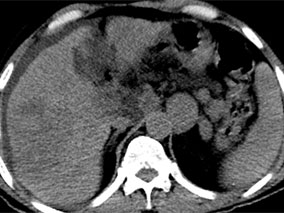

Le carcinome hépatocellulaire (HCC) est la plus fréquente des tumeurs primitives du foie. Il s’agit du 5e cancer par ordre de fréquence mais le 3e en terme de mortalité. Il se développe habituellement sur une hépatopathie chronique, virale ou toxique. Différentes modalités de dépistage par imagerie sont possibles : échographie (US), sans ou avec injection de micro bulles (technique à ce jour non approuvée par l’US Food and Drugs Administration), scanner (CT) ou imagerie par résonance magnétique nucléaire (IRM), elles mêmes généralement couplées à l’utilisation d’agents de contraste vasculaires, du fait de la nature typiquement hyper vascularisée de l'HCC.

Dans les autres situations diagnostiques, la sensibilité de l’US sans micro bulles était de 0,73 (IC 0,46-0,90) pour une spécificité de 0,93 (IC 0,85-0,97). Concernant le CT, elles étaient respectivement de 0,83 (IC 0,75- 0,89) et de 0,91 (IC 0,86- 0,96). Enfin, pour l’IRM, les valeurs étaient de 0,80 (IC 0,79- 0,93) et de 0,89 (IC 0,83- 0,93).Globalement, la sensibilité de l’US sans injection de micro bulles s’est montrée moindre que celle du CT ou de l'IRM, la différence combinée, à partir de comparaisons directes se situant entre 0,11 et 0,22. L’IRM apparaît plus sensible que le scanner (différence combinée : 0,09). L’écart entre US et CT est de moins 0,10. Les différences de sensibilité sont apparues plus marquées quand il s’agissait de petites lésions, inférieures à 2 ou 3 cm et quand étaient utilisés en IRM des agents de contraste spécifiques hépatiques, acide gadoxétique ou gadobenate plutôt que des agents non spécifiques tels que gadopentétate ou gadodiamide.

Lors de l’évaluation de lésions focales hépatiques, la sensibilité de l'US avec contraste est de 0,87 (IC : 0,79- 0,92) pour une spécificité de 0,92 (IC : 0,83- 0,95). Elle est de 0,86 (IC : 0,75- 0,92) pour le CT avec une spécificité de 0,88 (IC : 0,76- 0,98) et enfin de 0,75 (IC 0,65- 0,89) pour l’IRM, la spécificité se situant alors à 0,83 (IC 0,61- 0,93). Deux études confirment que la sensibilité de l’US avec contraste est supérieure à celle de l’US simple (différence 0,50, IC : 0,41- 0,58). La sensibilité de l’US avec contraste est plus faible que celle de l’IRM en cas de lésions de petite taille. Dans l’ensemble des travaux, la sensibilité est d’autant plus faible que les données de la biopsie hépatique sont prises pour référence, que les lésions sont de petite taille et qu’elles sont bien différenciées. Pour l’IRM, la sensibilité s’est aussi avérée inversement proportionnelle à la classe Child-Plug de l’hépatopathie. Pour l’US, l’influence de paramètres tels que la profondeur de ou des lésions ou l’indice de masse corporelle n’ont pas été évalués.

Ainsi ressort-il de cette revue systématique que l’US sans produit de contraste a, dans le cadre d’un programme de surveillance des HCC, une moindre sensibilité que le CT ou l’IRM, la différence se situant entre 0,11 et 0,22. Aucune disparité n’est constatée entre les 3 techniques dans l’évaluation des lésions focales hépatiques, l’IRM paraissant toutefois plus sensible dans la détection des lésions de petite taille. Le recours à des produits de contraste, tant pour le CT que l’IRM améliore la sensibilité. Les conclusions de cette revue diffèrent quelque peu de celles des publications antérieures qui, globalement, n’avaient pas montré de différence patente en ce qui concerne les sensibilités des 3 techniques d’imagerie. Cependant, plus de la moitié des publications sélectionnées étaient d’origine asiatique, et beaucoup excluaient les lésions hépatiques non hyper vasculaires. De plus, depuis 1988, date du début de la recherche bibliographique, les techniques ont continué à s’améliorer. enfin, un haut degré d’hétérogénéité statistique était présent entre les diverses études; seules celles de langue anglaise ont été retenues; des biais de publication restent toujours possibles; la disponibilité et les coûts financiers n’ont pas été appréhendés, ni enfin les possibles effets secondaires de chacune des méthodes d’imagerie.

En conclusion, dans le diagnostic des HCC, tant le CT que l’IRM sont associés à une plus grande sensibilité que l’US sans produit de contraste, l’IRM paraissant la plus performante. Dans l’évaluation des lésions focales hépatiques, les 3 techniques sont sensiblement équivalentes, avec une sensibilité moindre en cas le lésions de petite taille ou bien différenciées.